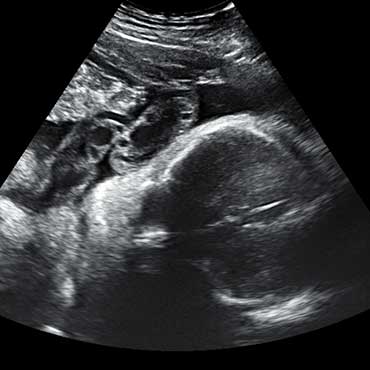

All photos are from our equipment and are of our actual clients.